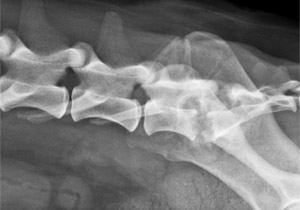

• Hernias discales

El Servicio de Neurología/Neurocirugía realiza procedimientos especializados como:

• Procedimientos quirúrgicos: patología discal, patologías congénitas, procesos traumáticos, neoplasias, ...